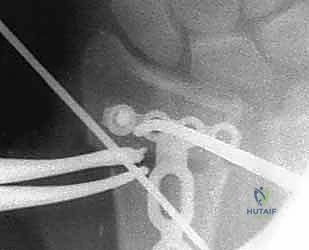

5. التثبيت بصفائح التيتانيوم (Internal Fixation)

للحفاظ على الوضع الجديد والمثالي للعظم، يتم استخدام صفائح تيتانيوم متقدمة ذاتية الغلق (Volar Locking Plates). هذه الصفائح مصممة تشريحياً لتلائم شكل الكعبرة، وتوفر تثبيتاً قوياً جداً يسمح للمريض ببدء تحريك أصابعه في اليوم التالي للعملية.

بناءً على التخطيط الثلاثي الأبعاد المسبق، يستخدم الدكتور هطيف مناشير عظمية دقيقة جداً لعمل شق في العظم في نقطة التشوه الأصلية. يتم فتح العظم وتعديل زاويته واستعادة طوله الطبيعي.